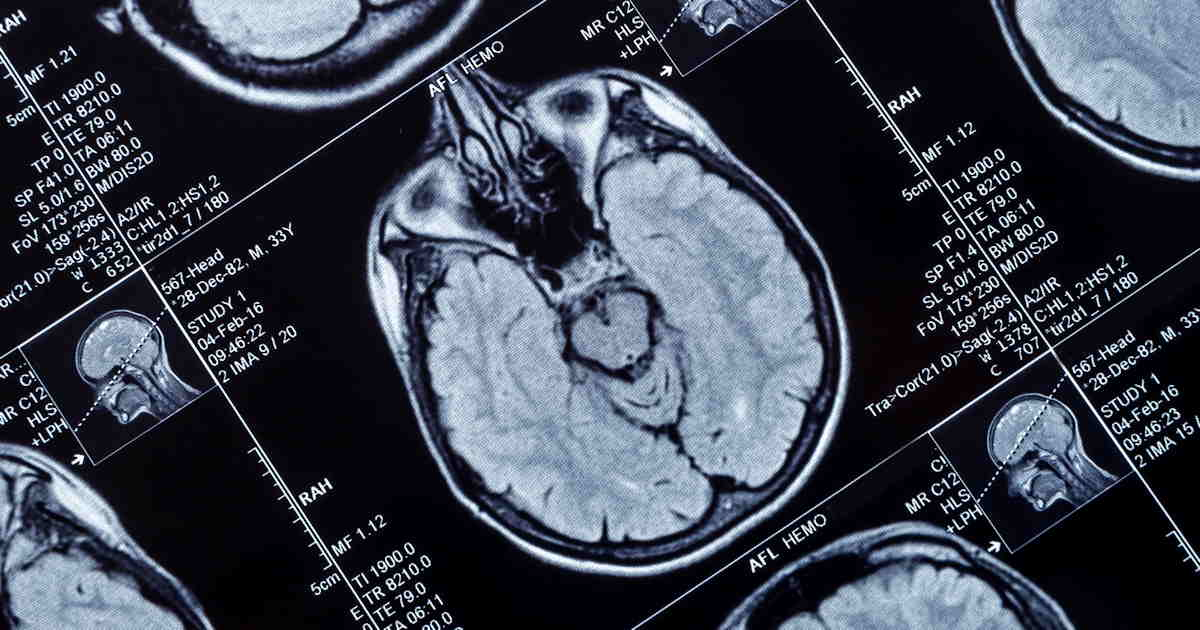

Bayer has initiated phase III studies of its investigational macrocyclic gadolinium-based contrast agent (GBCA) gadoquatrane.

Bayer's clinical development program is called QUANTI and includes two phase III studies in adults and one pediatric study investigating gadoquatrane for use in MRI across all body regions and across ages from birth to adulthood, the company said.

All trials are investigating gadoquatrane at a dose of 0.04 mmol Gd/kg body weight. The aim of the trials is to demonstrate the lowest gadolinium dose for an MRI contrast agent, Bayer said.